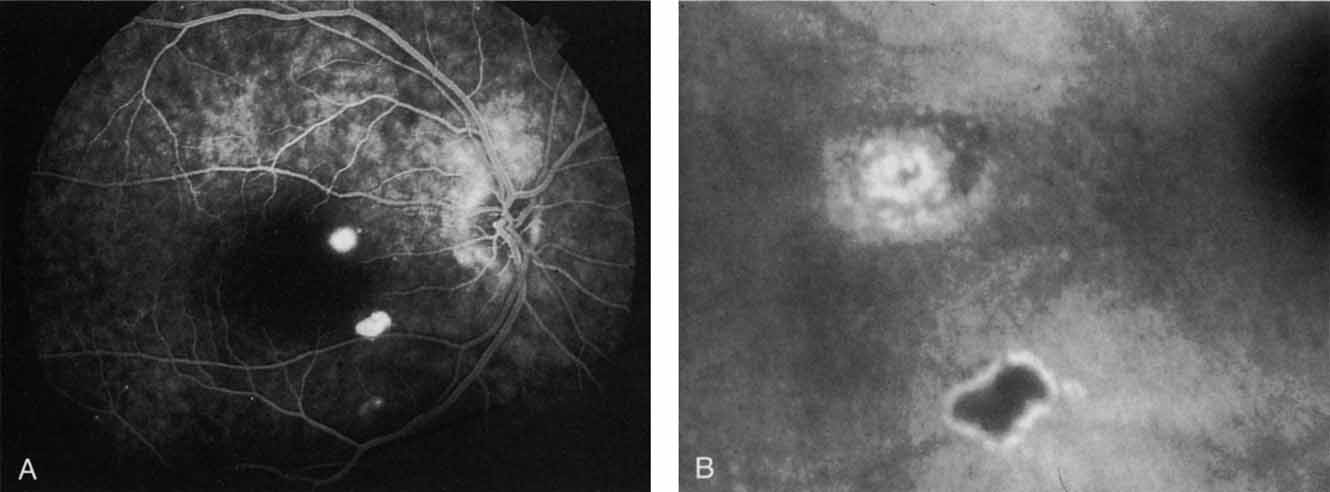

Most promising in this category of inflammatory choroidopathies is a better detection and understanding of the lesions of multifocal choroiditis. Multiple large, scattered, hypofluorescent spots are seen on ICG angiography, particularly in the later phases of the angiogram69 (Fig. 18). These lesions are not evident either on clinical examination or on fluorescein angiography. In addition to having these larger hypofluorescent lesions, patients with multifocal choroiditis have smaller dot-like lesions and hyperfluorescent foci that do not correlate with lesions seen clinically or by FA. They involve the posterior pole and in some patients extend into the mid-periphery. There is also a “papillotropic” involvement, with confluent hypofluorescent lesions surrounding the optic nerve,69 which may be useful in understanding the associated blind-spot enlargement evident in this condition.70 Other zonal visual field defects have been associated with this condition,70 and corresponding ICG abnormalities have been documented in some patients.69

Fig. 18 A. Clinical photograph of a patient with active inflammation associated with multifocal choroiditis. An atrophic scar from previous laser photocoagulation treatment is noted in the temporal macula. The patient reported visual disturbance, and an enlarged blind spot was noted on visual field testing. B. Late-phase indocyanine green study demonstrating a multitude of hypofluorescent spots that were larger than those seen with multiple evanescent white dot syndrome and more numerous and more extensively distributed than appreciated on clinical examination. Note that there is marked confluence of these lesions around the optic nerve, which may help to explain the enlarged blind spot noted on visual field testing.

Natural history data indicate that with progressive increase in vitritis and associated choroidal inflammation, an increase in the number and extent of these hypofluorescent lesions can be documented.40 Furthermore, use of oral steroid therapy as a means of controlling this inflammatory process has been documented to produce not only clinical resolution of the inflammatory process but also corresponding resolution of the hypofluorescent lesions seen on ICG angiography.69 These clearly demonstrated lesions not only may lead to a better understanding of the process of inflammation involved in multifocal choroiditis and potential management strategies but also may serve to differentiate this condition from the ocular histoplasmosis syndrome.